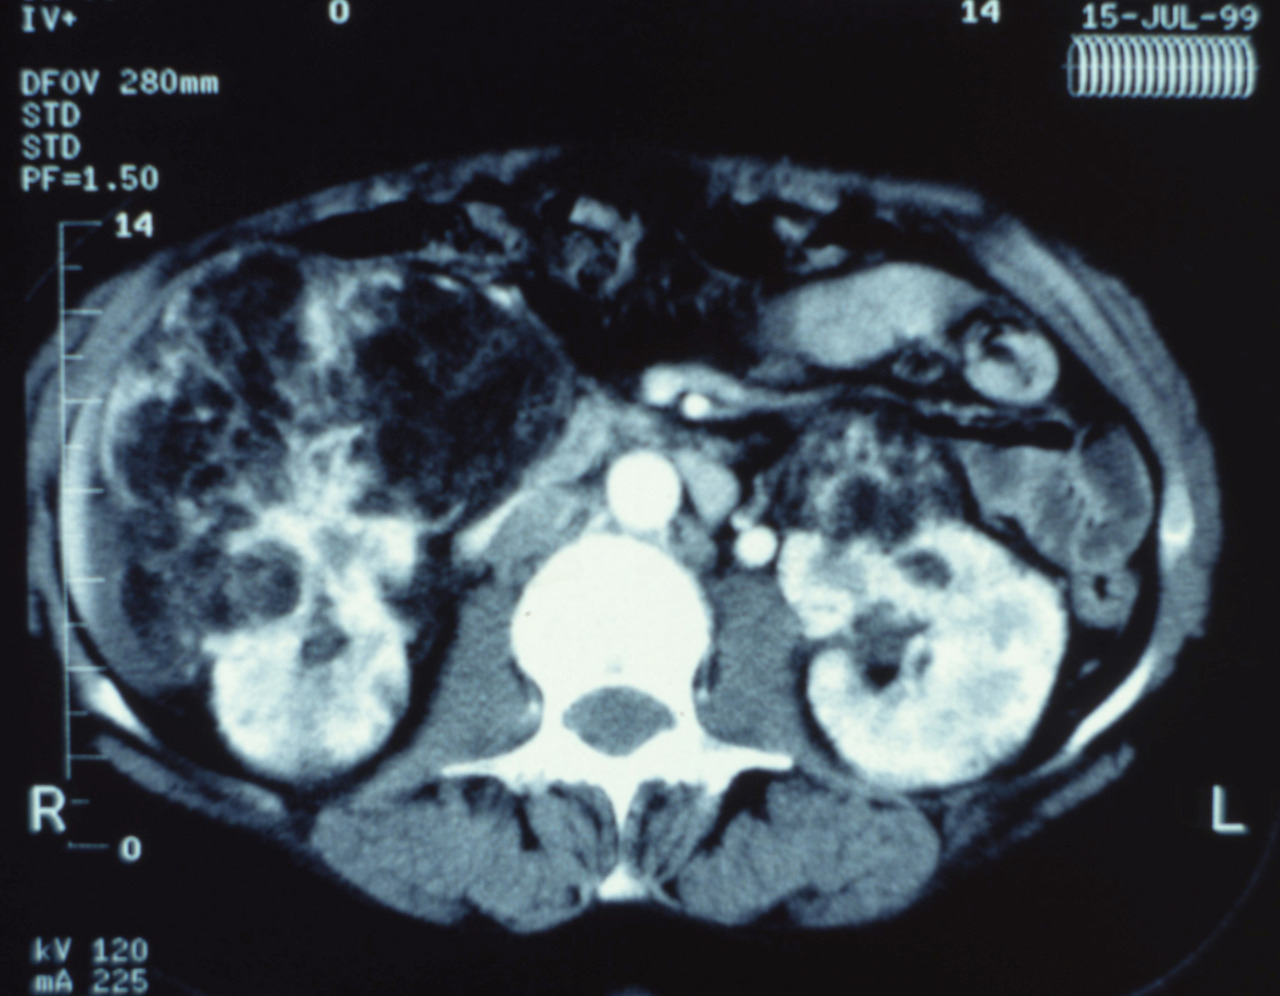

Quel est votre diagnostic ?

Il s'agit de l'aspect radiologique d'un angiomyolipome du rein droit. Il s'agit d'une tumeur bénigne, qui présente trois composantes différentes : musculaire, vasculaire et graisseuse, dont la distribution est variable. L'angiomyolipome se présente le plus souvent comme une tumeur unique, volumineuse, asymptomatique, découverte à la cinquième décennie chez la femme et survenant dans la majorité des cas en dehors de tout contexte de phacomatose (dans la sclérose tubéreuse de Bourneville il existe une atteinte rénale bilatérale et multiple). L'expression clinique est directement fonction de la taille ; environ 80 % des lésions de moins de 4 cm sont asymptomatiques, alors que 80 % des lésions de plus de 4 cm s'expriment par une douleur lombaire ou une hématurie. Le diagnostic d'angiomyolipome repose sur l'examen tomodensitométrique abdominal, qui va permettre la mise en évidence d'une composante graisseuse quasi-pathognomonique. La fréquence des remaniements hémorragiques de ce type de lésion d'une part, la nécessité d'un diagnostic différenciel avec une lésion rénale maligne d'autre part, nécessitent de définir une stratégie adaptée diagnostique et thérapeutique. Un angiomyolipome unique, de moins de 4 cm de diamètre, nécessite une surveillance radiologique au moins tous les deux ans. Par contre, lorsqu'il existe un doute diagnostique ou une suspicion de tumeur maligne, l'exploration chirurgicale avec un examen extemporané s'impose.